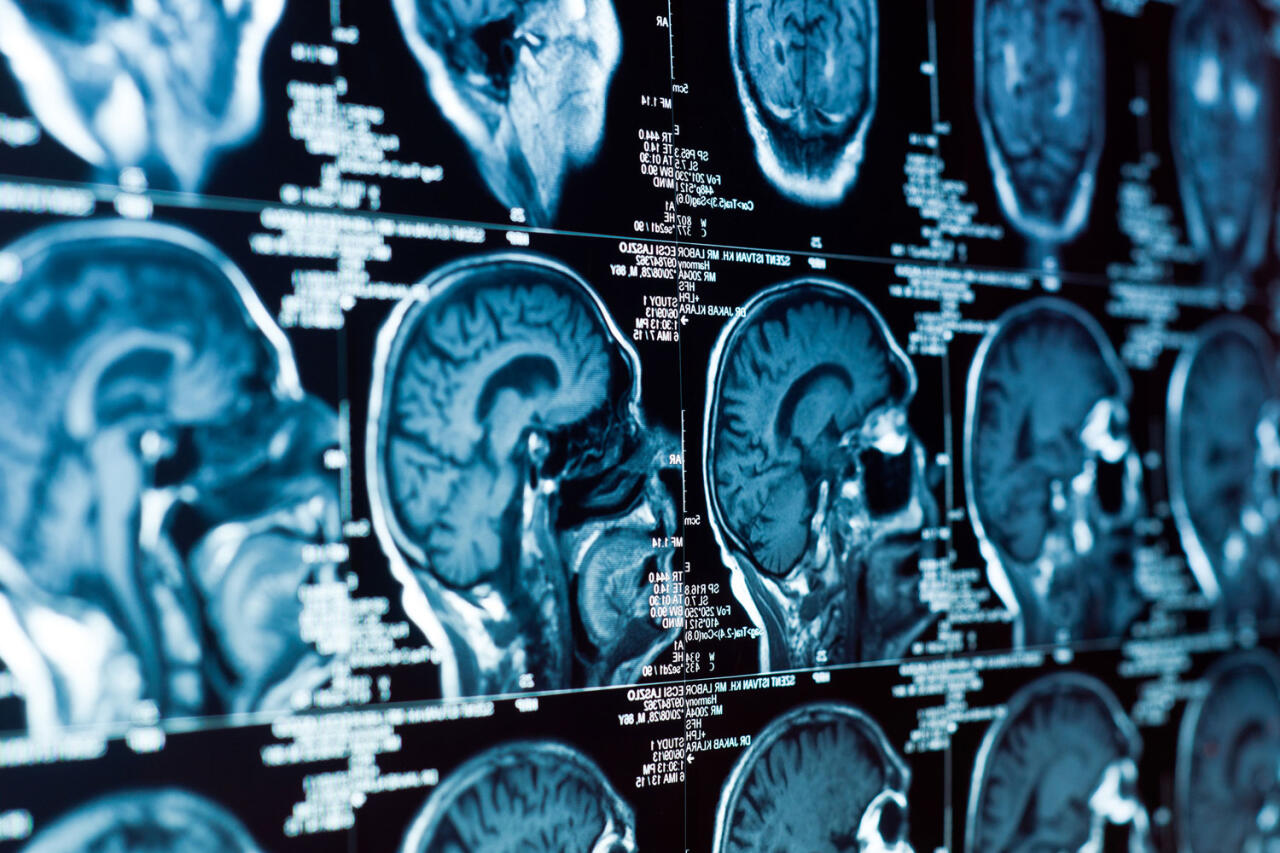

Жизнь в одиночестве оказалась токсичной для мозга

У крыс, которые жили в одиночестве, начали проявляться серьезные нарушения памяти и когнитивной гибкости. По словам ученых, такой эффект был схож с результатом отравления токсинами. Выполнение умственных задач для животных из второй группы требовало больших усилий - нейроны передней поясной коры активировались интенсивнее, что свидетельствовало об истощении ресурсов.

В то же время у социализированных крыс когнитивные способности сохранялись на уровне молодых особей. В гиппокампе грызунов из второй группы также не наблюдалось значительного снижения активности в области CA3, ключевой для памяти и обучения.